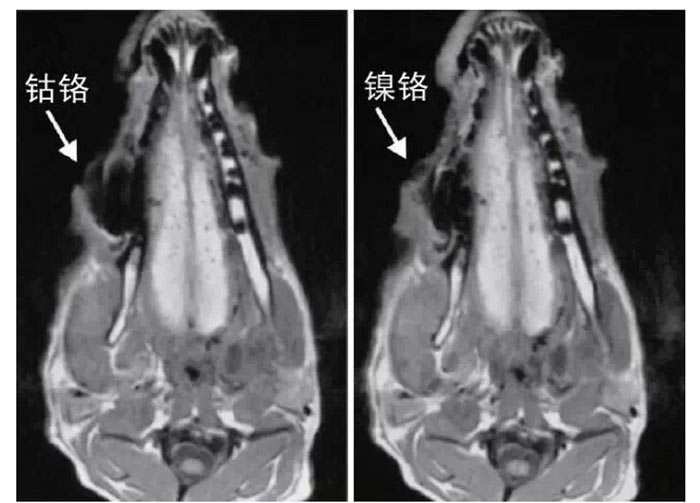

文獻研究中常使用的金屬包括鎳鉻合金、鈷鉻合金、低鈦合金、純鈦、金合金、金鈀合金、銀鈀合金等成分如表所示。大量研究得出近乎一致性的結論。金合金、金鈀合金、銀鈀合金對MRI影響甚微,與全瓷材料、丙烯酸樹脂極為相似,表現為修復體影像邊緣光滑、無變形、無偽影;純鈦金屬對MRI影響較小,接近于全瓷材料;但有的研究卻發現純鈦在核磁共振場中也產生偽影,但偽影涉及的掃描層數較少;低鈦合金(鈦合金)對MRI影響較大,介于純鈦和鎳鉻合金之間,中度偽影;鎳鉻合金、鈷鉻合金對MRI影響很大,鈷鉻合金更甚;表現為重度偽影、圖像扭曲變形(圖1、圖2)。不難看出,對MRI 影響,全瓷材料、樹脂材料<金合金等貴金屬<純鈦<低鈦合金<鎳鉻合金<鈷鉻合金。有研究發現鈷鉻合金橋偽影大小與修復體長軸一致,影響范圍為固定橋近遠中徑2倍,頰舌徑的4倍;相同外形金屬修復體厚度增加,偽影增加。單個金屬樁核偽影可波及到上頜竇、牙槽骨、舌體、舌下腺等組織器官,但對眼底、眼內容物、腦組織和頸椎成像基本無影響。

圖2 4種金屬冠在犬MRI檢查中的影響,圖片引自《實用口腔醫學雜志》2014第30期《4種金屬冠對磁共振成像影響的對比研究》一文,作者高嵐等